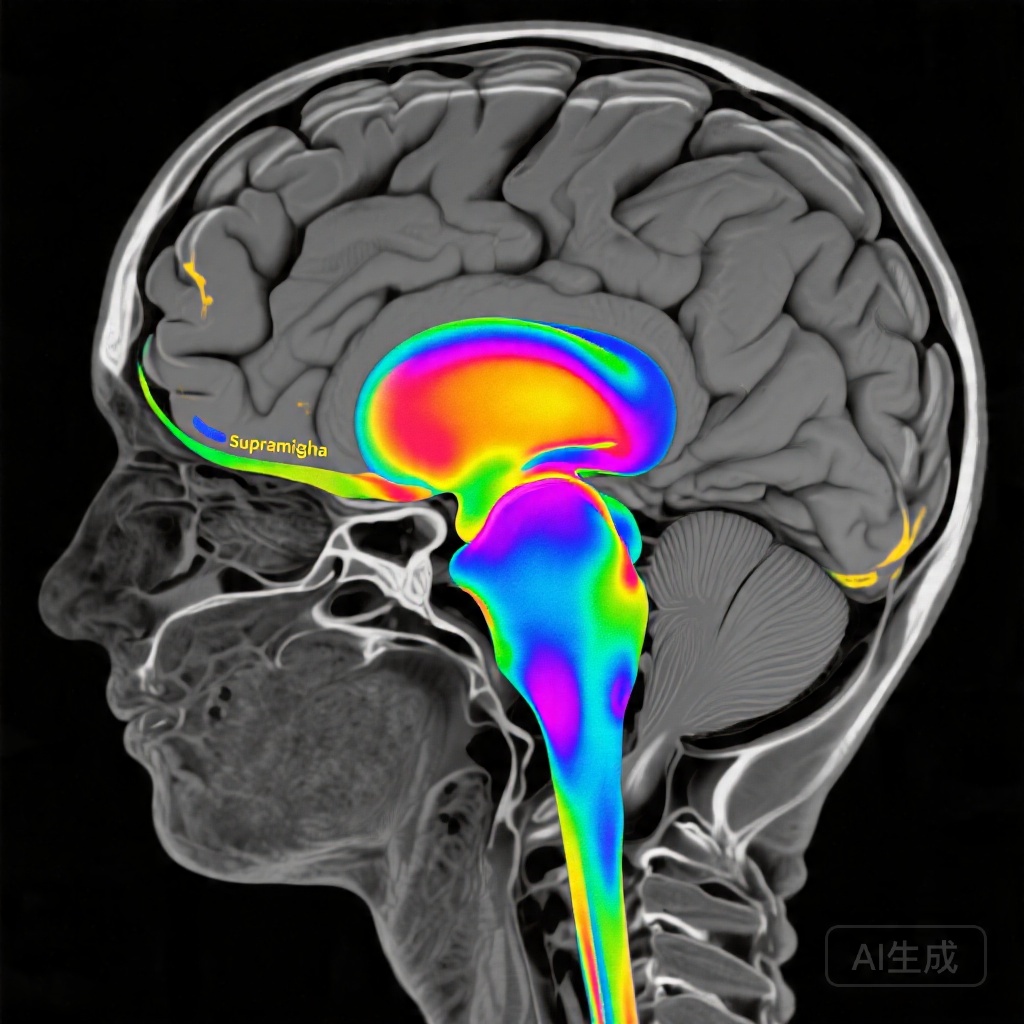

实时fMRI神经反馈的出现提供了一种有前景的神经调节策略,使患者能够可视化并有意识地调节与语言功能相关的特定区域的大脑活动。与经颅磁刺激或经颅直流电刺激不同,fMRI神经反馈提供了来自目标区域的基于血流动力学的直接反馈,可能允许更精确地靶向任务特定的神经回路。左侧缘上回是背侧语言通路的关键枢纽,在音位处理和字母-音位转换中起着重要作用——这些技能对于准确阅读尤其是新词或非单词刺激至关重要。

基于任务的功能成像分析显示,条件性神经反馈组和非条件性神经反馈组在训练相关的激活模式方面存在显著差异。条件性神经反馈中风组在干预后的扫描会话中表现出左缘上回显著的激活增加(z=4.7;簇家族错误校正P=0.05),并在更广泛的阅读网络中扩展激活,特别是在非单词阅读试验中尤为明显。这种在语音要求较高的任务中定位到特定阅读区域的激活表明,神经反馈成功地强化了在行为相关处理过程中目标区域内的活动。